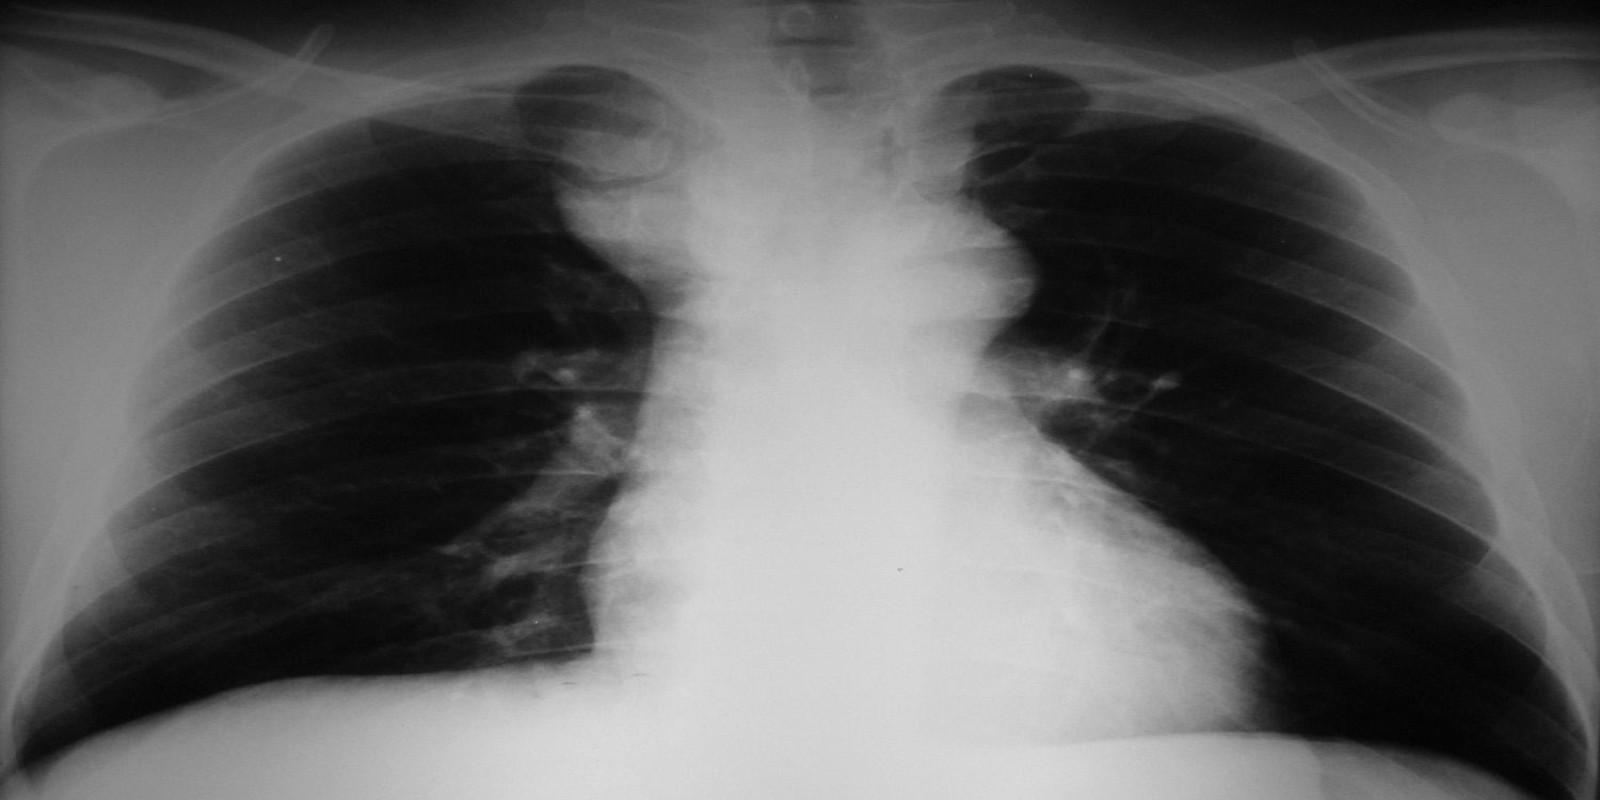

Tireóide ectópica mediastinal

Ectopic Mediastinal Thyroid